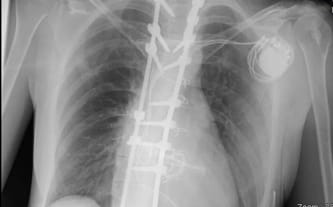

Dostaliśmy kolejną złą informację. Zastawka mitralna serca nie działa tak, jak powinna, wyniki są coraz gorsze. Potrzebna kolejna operacja serca. W 2019 roku stałam się posiadaczką sztucznej zastawki serca, której żywotność wynosi około 10 lat. W przyszłości potrzebna będzie kolejnej operacja, aby ją wymienić. Jakby tego było mało, pojawiło się powikłanie pooperacyjne – elektryka serca nie działała, nie jest w stanie bić już samodzielnie. Zapadła kolejna decyzja – potrzebny rozrusznik serca. Żyję więc z nim od tamtej pory i będę od niego zależna już do końca życia.

Zaczęłam szukać ortopedy, który naprawi moje plecy, a przy okazji nie uszkodzi już schorowanego serca. W styczniu 2023 roku przeszłam operację stabilizacji kręgosłupa. Do mojej kolekcji implantów dołączyły 2 długie pręty, kilkanaście śrub oraz trochę drutu. Wszystkie te elementy możesz dostrzec na moim zdjęciu rentgenowskim.